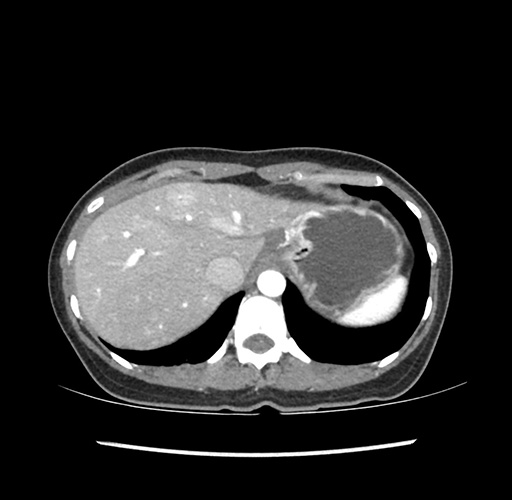

Imaging Analysis

Look through the patient's CT scan to identify any areas of concern for the necessary procedure.

Based on your CT findings, which issue(s) would give reason for "planned slowing down moment(s)" in this case?

Considering a standard left lateral sectionectomy procedure, what step(s) of the operation would you do differently in this case ?